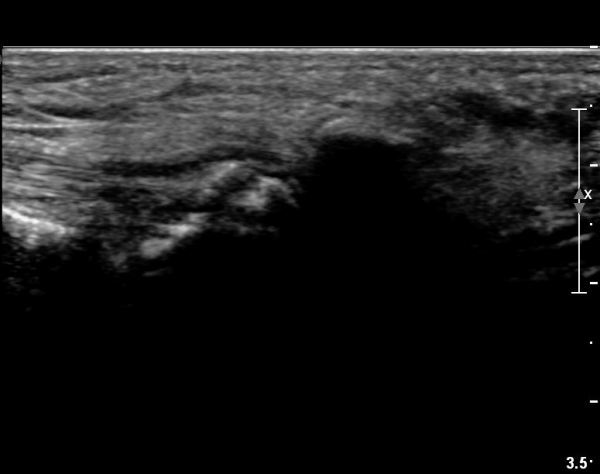

±¹¼ÒÀû ¾ÐÅëÀ» º¸ÀÌ´Â ÁßÁ·°ñÀÔ¹æ°ñ °üÀý ¹Ù´ÚÃø¿¡ ŽÃËÀÚ¸¦ ´ë´Ï Á¾ÀÚ»ÀÀÇ °¡ µÎ Á¶°¢À¸·Î

°üÂûµÇ°í Á¾ÀÚ»À ±ÙÀ§ºÎ¿¡ Àú¿¡ÄÚ ¿¬ºÎÁ¶Á÷ ºÎÁ¾ÀÌ °üÂûµÇ°í µÎ Á¾ÀÚ»À »çÀÌÀÇ »À Ç¥¸éÀÌ °ÅÄ£

¾ç»óÀ» º¸ÀÓ(»çÁø 1).